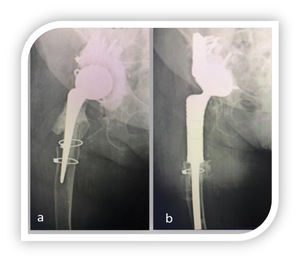

At last follow-up all implants were osteointegrated even in presence of thin striae of femoral radiolucency in most reported cases. In particular 16 radiolucency were noticed (3 in periprosthetic fractures, 7 in periprosthetic osteolysis and 6 in recalcitrant infections). No patients showed clinical symptoms related to radiolucency.